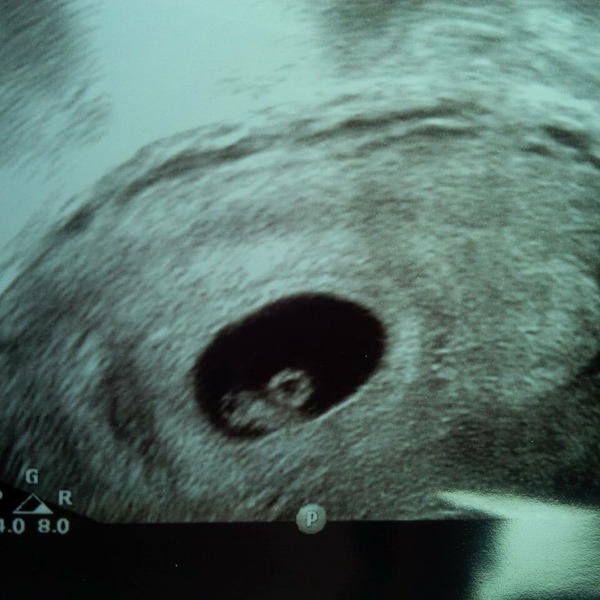

So, I went for my 7 week scan yesterday! Was v nervous as we had an increased chance of an ectopic so was just hoping for good news. The nurse commented on how worried I looked but I explained it had been a pretty horrendous year fertility wise given I had an ovary removed this time last year and then a long wait for IVF! So she put me at ease and said not to worry if we couldn't detect a heartbeat as 7 weeks is still early.

I had an internal scan and the first thing she said was that it was all in the right place so not ectopic!! By this point I could feel my eyes starting to well up, so relieved. Then she said she would look for the heartbeat and it came up immediately! I can't tell you how amazing it was to see it, beating away so fast on the screen. The nurse said "your baby is saying hello straightaway"!! By this time obviously the tears were rolling down my cheeks (happy relieved ones though) SmileGrinSmile

Think seeing the little heartbeat made it feel real for DH too. Could see his eyes glistening too (he NEVER cries). He kept saying yesterday "I'm going to be a dad!"

Here is a pic of our little bean Smile

Oh Bel, I've just blubbed reading your post! Look at your perfect little baby!! So happy for you xx

Oh wow Bel that is incredible and totally welling up all over the place for you. Look at the bean!! You can see it's a baby and everything! So happy for you, what an amazing day SmileSmileSmile

Lovely scan photo Bel it looks a lot less like a seahorse/blob like the scans on apps, so nice to get a clear picture.

Bel that is an amazing scan picture, I'm so happy for you.

Bel great scan. I don't think I've ever seen one so clear this early. You must be so happy.